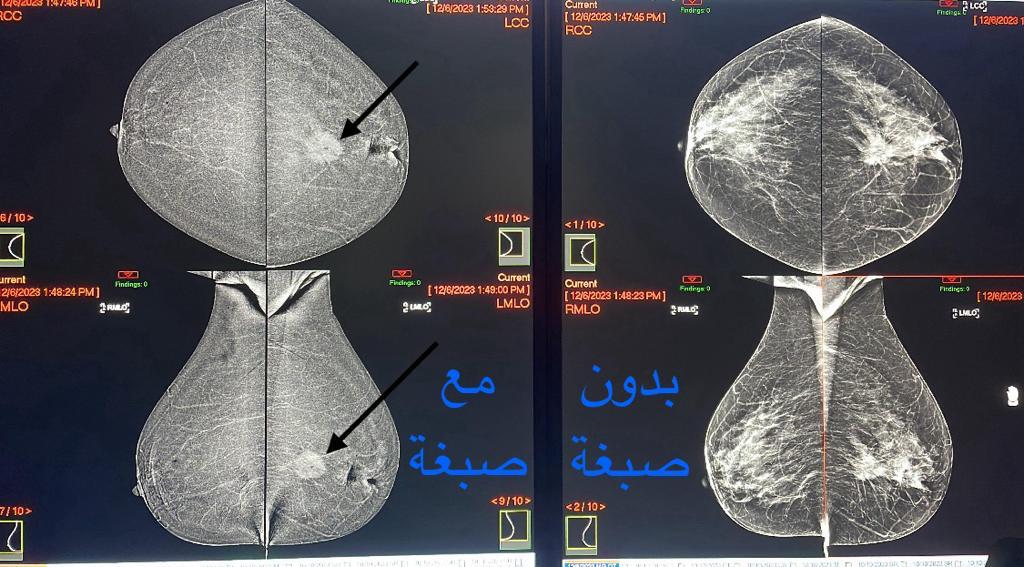

كشفت مدينة الملك سعود الطبية عضو تجمع الرياض الصحي الأول عن البدء بالعمل على تقنية جديدة و لأول مرة على مستوى المدينة والمتمثلة بتصوير الماموغرام بتقنية الصبغة (CEM) والتي تحمل وعدًا كبيرًا لإنقاذ الأرواح، وثورة في إدارة سرطان الثدي.

وأوضحت استشاري أشعة الثدي د.آلاء الحازمي بأن تقنية (CEM) تعد أداة حيوية في مكافحة سرطان الثدي، وذلك من خلال التغلب على قيود التصوير بالماموغرام التقليدي، وتعزيز قدرة الأطباء على اكتشاف وتشخيص الأورام الثديية بشكل أدق وأسرع، مما يساهم في تحسين النتائج العلاجية وسرعتها، وبالتالي زيادة الأمل في مكافحة سرطان الثدي.